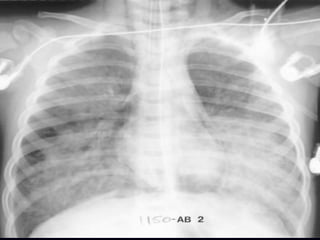

Adult Respiratory Distress Syndrome

Non-cardiogenic pulmonary edema

Distinguishing characteristics:

Normal size heart

No pleural effusion